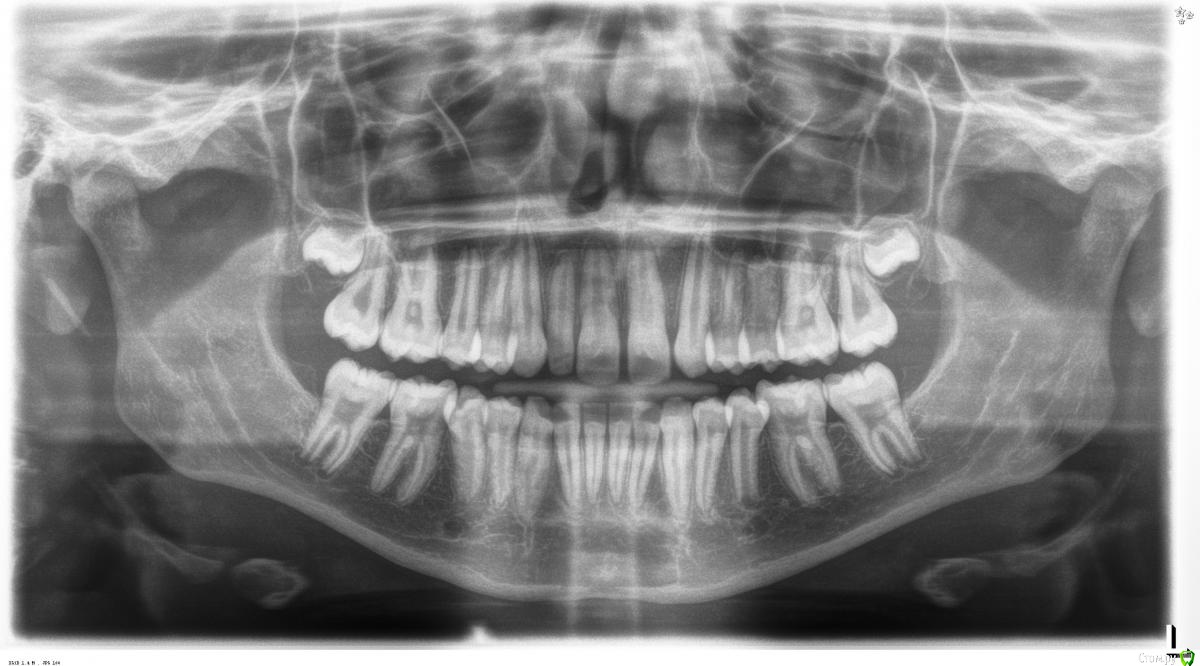

Illina Опубликовано 2 августа, 2019 Поделиться Опубликовано 2 августа, 2019 Добрый день! Девушке 18 лет.Нет левой верхней двойки, из-за чего между зубами верхними щели.Не улыбается прилюдно(Консультировались лет в 16 у ортодонта, сказал ждать 18 лет. Читала про 2 тактики - 1) смещение зубов с целью убрать щели и 2) имплантацию отсутствующей двойки. Цель самой девушки - избавиться от щели, то есть наверное 1 вариант бы устроил.Но будет ли результат постоянен? Не раздвинутся ли зубы после снятия брекетов опять?? Спасибо Ссылка на комментарий

Brigita Опубликовано 5 августа, 2019 Поделиться Опубликовано 5 августа, 2019 Я за имплант в этом случае. Брекеты можно и сейчас,получить место, имплантацию в 18.После снятия брекетов вариантов замещения с сохранением места множество Ссылка на комментарий

Brigita Опубликовано 5 августа, 2019 Поделиться Опубликовано 5 августа, 2019 Спасибо.Ей уже 18... А скажите пожалуйста, вы за имплант - из-за того, что иначе разъедутся зубы опять?Или просто недостаточно красиво на ваш взгляд, если просто стянуть их?потому что1. это будет некрасиво2. нестабильно3. несимметрично. Чтобы было симметрично, нужно вторую двойку удалить. Но клыки крупнее двоек и на фоне центральных резцов это будет1. некрасиво Ссылка на комментарий